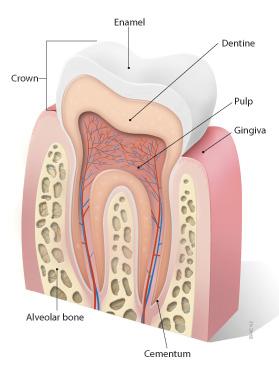

10

11

12

13

baby teeth

Permanent Teeth

Incisors (8)

16

Permanent Teeth

Premolars (8)

18

Permanent Teeth

Crown

Neck

Root

Alveoli

Gingiva

Enamel

Dentin

Cementum